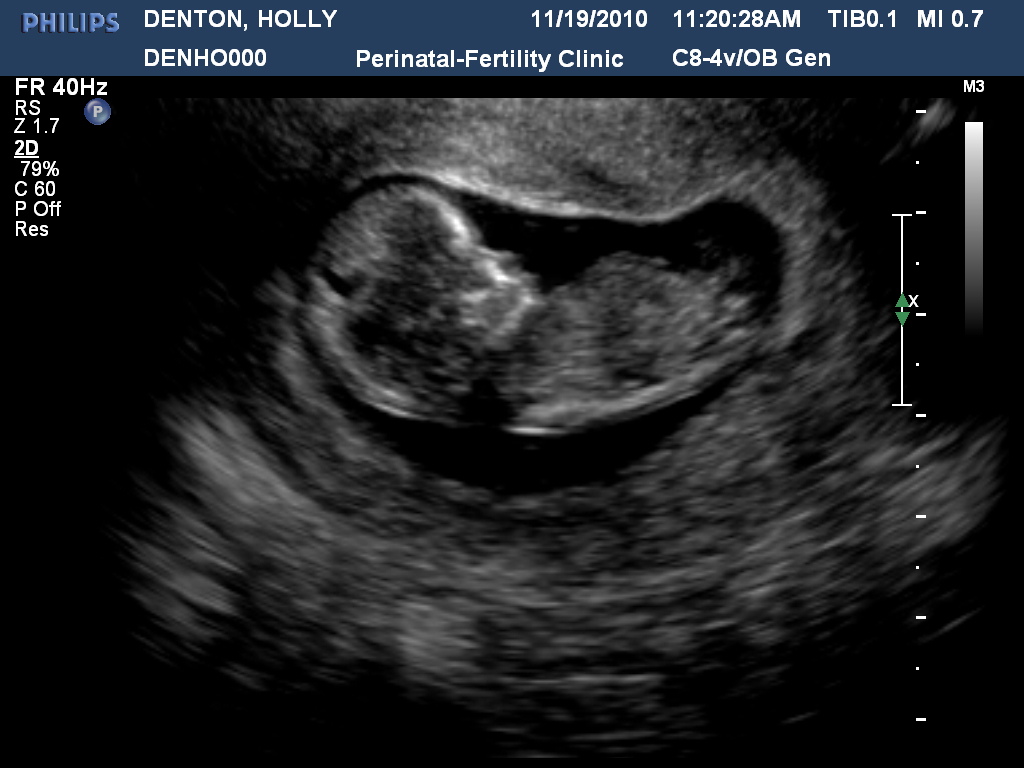

Today was another good visit at the high risk doctor! Mom came down from Huntsville on Sunday so she has been with me all this week which has been fun! She got to come to the sono today and see the baby wiggling and sleeping. Baby was much less active today baby was sleeping being still and behaving while we got all the measurements we needed for the nuchal scan. Heart rate was 170 even which it stays pretty high. It was neat to see the baby again and I will post tons of pictures and a video of the baby today on the blog god willing I figure out how to do that all! I have been doing great blood pressure wise on the low sodium diet. Even though the low sodium diet has to be one of the hardest diets to follow because everything you can think of is HIGH in sodium it is no wonder we have so many heartattacks in this day and age! I know I will be forever changed. But being pregnant on this diet with cravings that drive me up the wall totally SUCKS BUTT! Because I just can't have what I want. I just remember I am doing this to hold a baby in my arms. If me sucking it up with help that baby not be in the NICU any days I will totally do it! I have been really good and NOT cheated ONCE! I am so very very proud of myself the only day I will eat whatever will be on holidays for that day only though leftovers don't count. LOL I will ask family to help me out a little and maybe skip on the salt and use unsalted butter aswell. If they are willing. We saw some good friends at the doctor's today aswell Melissa and Pat Crowder! Melissa is Due in January with a precious little girl! She was looking good and ready for that baby to be out soon! LOL I can't wait until I am at that point in the home stretch! Sooooonnnn! Also bought my first round of maternity cloths today too! As I am down 16 pounds now but belly is pouching and getting round can't fit into any jeans or pants that I have and boobs are making all my shirts short! Well now picture time!!